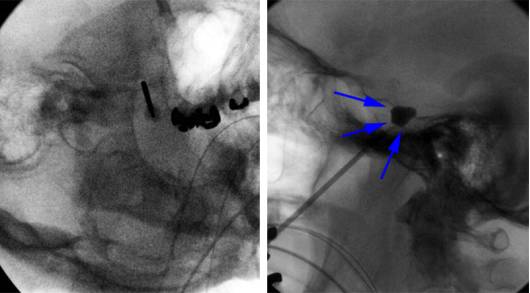

图4. 针尖抵达颅底卵圆孔(左图);微球囊向三叉神经分支走向的眶上裂、圆孔和卵圆孔轻微扩张(右图箭头)。

图5. 上方过度充盈的球囊会压迫海绵窦内外展神经导致神经麻痹。若球囊形态不佳,可能是因为导管尖端移位至Meckel’s 腔外侧而进入中颅窝,此时应抽掉造影剂并重新调整导管位置。